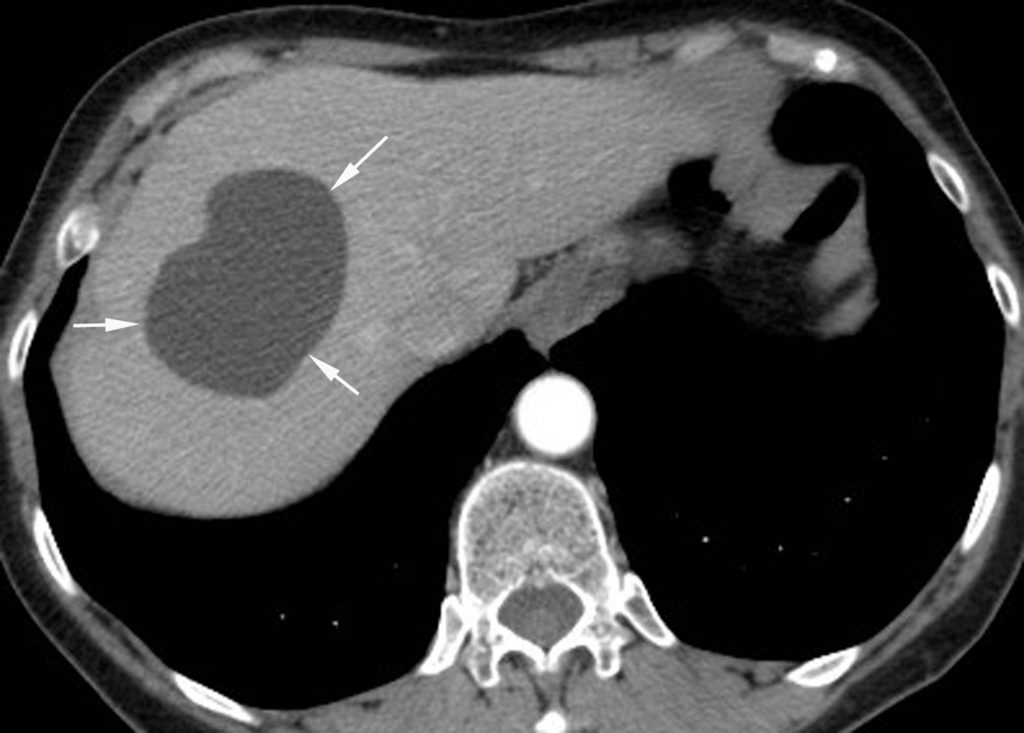

- de densité liquidienne en scanner ne se rehaussant pas après injection (figure 16.10) ;

Fig. 16.10. Coupe scanner après injection de produit de contraste iodé d’un kyste hépatique simple (flèches). Le kyste se présente comme une formation hypodense de densité liquidienne (11 UH sur cet exemple). Il n’y a pas de paroi, de cloison ou de végétation.

Source : CERF, CNEBMN, 2022.